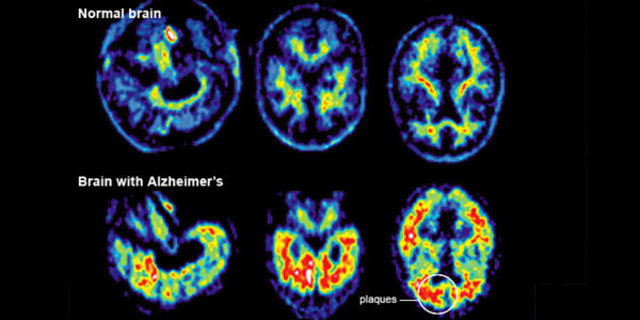

Unutkanlığın nedenleri oldukça fazladır. Genç popülasyonda unutkanlığa yol açan nedenlerin tamamı ileri yaşlarda da unutkanlığa yol açabilir. Ancak, sadece ileri yaşlarda görülen ve unutkanlığa yol açan bazı hastalıklar (Alzheimer hastalığı, frontotemporal demans gibi) genç yaşlarda unutkanlığa yol açmaz.

Yaşlılarda ise daha çok; Alzheimer hastalığı, vasküler (damarsal) nedenli unutkanlıklar, Lewy cisimcikli demans (bunama), parkinson hastalığı-demans kompleksi, normal basınçlı hidrosefali gibi nedenler bellek fonksiyonlarında bozukluğa neden olduğu gibi, gençlerde unutkanlığa neden olan faktörler de yaşlılarda hafıza bozukluklarına neden olabileceği unutulmamalıdır.

Unutmayınız ki, Alzheimer hastalığı gibi nörodejeneratif bunamalarda unutkanlık belirtisi ortaya çıkmadan yaklaşık 10-15 yıl önce beyinde değişiklikler başlamaktadır. Ancak unutkanlık check-up’ı ile erken dönemde silik de olsa bazı bulgulara tespit edilebilmektedir.